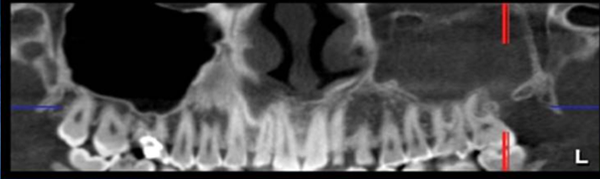

Medium F.O.V CBCT

Maxilla or Mandible.